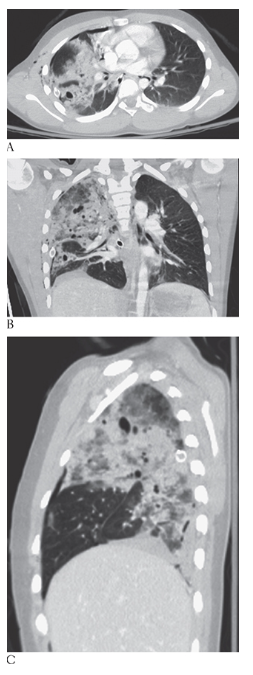

What is A

Lung Contusion. CECT axial coronal MPR

What is B

Lung Contusion. CECT axial and sagittal MPR

What is C

Lung Contusion. CECT axial images of a trauma patient showing the extensive pulmonary contusion of the right upper and lower lobes. There is confluent lung opacification with multiple small posttraumatic pneumatoceles.